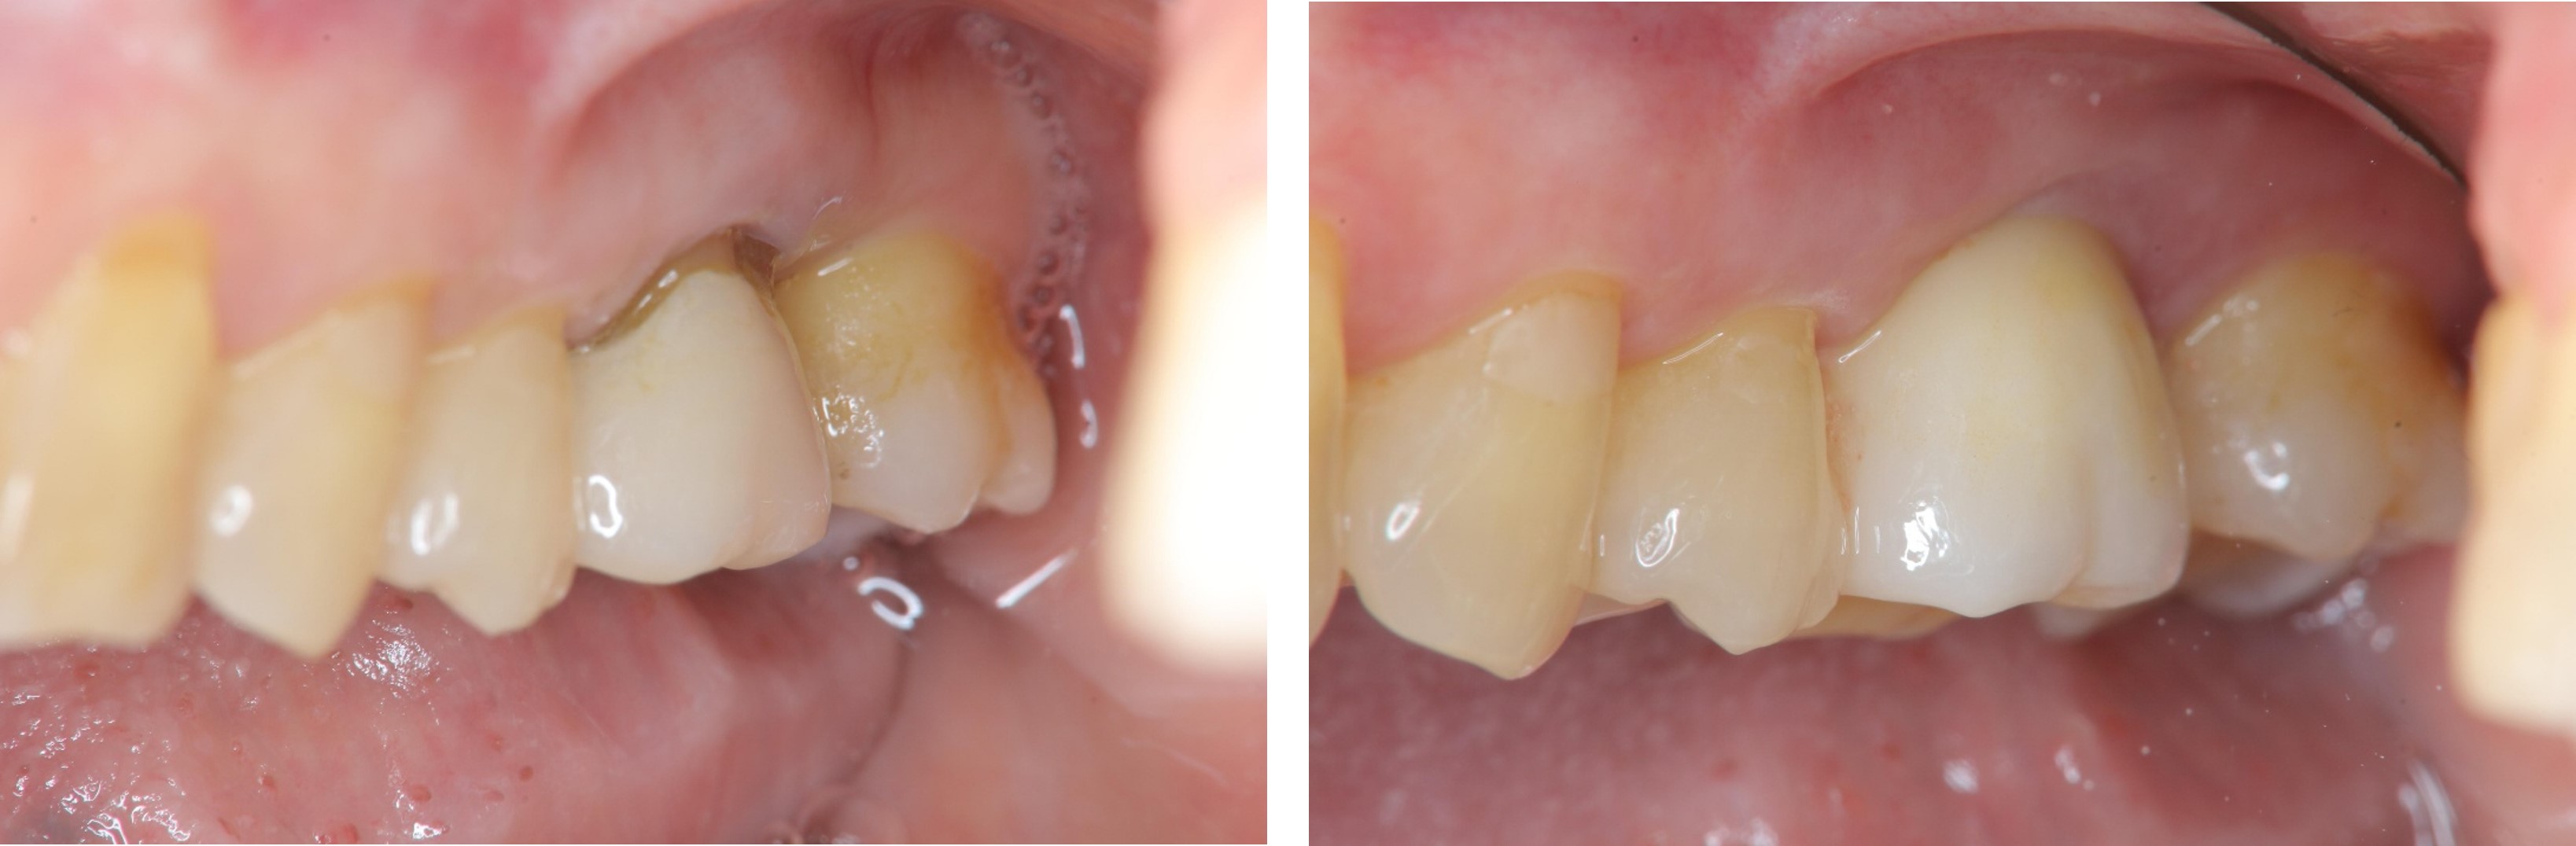

治療前,根管後大臼齒有牙裂

治療前,根管後第一大臼齒有牙裂

治療前,根管後大臼齒根部有蛀牙裂

術前、術後比較